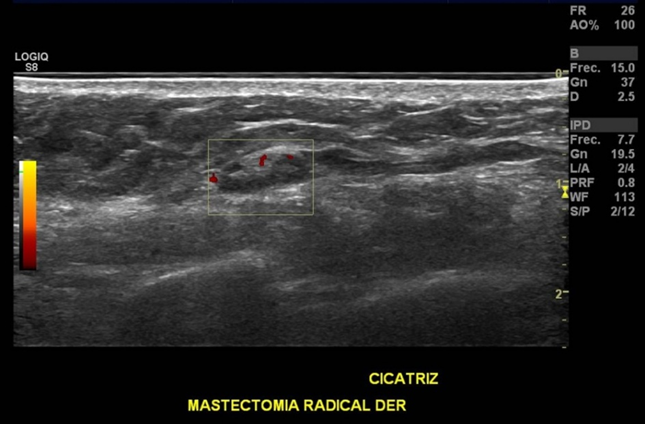

• Cicatrices en mama derecha por mastectomía radical y vaciamiento ganglionar derecho.

Se evalúa en forma dirigida sitio de mastectomía derecha, observándose presencia de linfonodo de tamaño y morfología normal en región de cicatriz.

Probable linfonodo en región de cicatriz de mastectomía derecha.